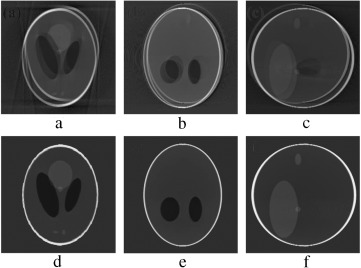

(a–c) Projection at 160°, 180° and 200° source position. (d–f) Axial, coronal ...

Figure 7.

(a–c) Projection at Failed to parse (MathML with SVG or PNG fallback (recommended for modern browsers and accessibility tools): Invalid response ("Math extension cannot connect to Restbase.") from server "https://mathoid.scipedia.com/localhost/v1/":): {\textstyle 160\mbox{°}}

, Failed to parse (MathML with SVG or PNG fallback (recommended for modern browsers and accessibility tools): Invalid response ("Math extension cannot connect to Restbase.") from server "https://mathoid.scipedia.com/localhost/v1/":): {\textstyle 180\mbox{°}}

and Failed to parse (MathML with SVG or PNG fallback (recommended for modern browsers and accessibility tools): Invalid response ("Math extension cannot connect to Restbase.") from server "https://mathoid.scipedia.com/localhost/v1/":): {\textstyle 200\mbox{°}}

source position. (d–f) Axial, coronal and sagittal slices of the translational motion corrupted reconstructed volume.

In order to validate the functionality of our proposed Marker-Based Motion Detection (MBMD) and artifacts mitigation technique (MB_FDK algorithm), we need to first simulate motion artifacts using our modified 3D Shepp–Logan phantom. For simulating motion artifacts, we need to perturb the 3D Shepp–Logan phantom during data acquisition time. Using the modified X-ray projection equation  [17] , which incorporated three translational Failed to parse (MathML with SVG or PNG fallback (recommended for modern browsers and accessibility tools): Invalid response ("Math extension cannot connect to Restbase.") from server "https://mathoid.scipedia.com/localhost/v1/":): {\textstyle (t_x,t_y,t_z)}

and three rotational (roll, pitch, yaw ) parameters of motion, we simulated several abrupt and gradual variations of motion on the 3D Shepp–Logan phantom. The cone-beam parameters listed in  Table 2  are used for our simulation. For abrupt variation of motion, we perturbed the 3D Shepp–Logan phantom with three different types of motion (translational, rotational, and rotational & translational combined) in three different test cases. Some of the images of motion corrupted projections and the axial, coronal and sagittal slices of the reconstructed volume of the above cases are plotted in  Figure 7 , Figure 8  and Figure 9 . For gradual variation of motion, we varied each parameter of motion separately in six different test cases. For gradual translational motion corruption cases, we gave ±6 mm of perturbation with a step size of ±1 mm. For gradual rotational motion corruption cases, we gave perturbation of ±5° with a step size of ±1°. The axial, coronal and sagittal slices of the gradual motion corrupted cases (+ perturbation only) are plotted in  Figure 10a  and Figure 10b .  Figure 10a  and Figure 10b  show the motion artifacts created in the reconstructed image due to the gradual perturbation given to the 3D Shepp–Logan phantom during data acquisition time. In Figure 10a , the 1st row shows the artifacts occurred due to the perturbation of +6 mm with a step size of +1 mm along the Failed to parse (MathML with SVG or PNG fallback (recommended for modern browsers and accessibility tools): Invalid response ("Math extension cannot connect to Restbase.") from server "https://mathoid.scipedia.com/localhost/v1/":): {\textstyle X}

-axis given. The 2nd and 3rd rows show the artifacts created due to the similar perturbation given to the phantom along the Failed to parse (MathML with SVG or PNG fallback (recommended for modern browsers and accessibility tools): Invalid response ("Math extension cannot connect to Restbase.") from server "https://mathoid.scipedia.com/localhost/v1/":): {\textstyle Y}

and Failed to parse (MathML with SVG or PNG fallback (recommended for modern browsers and accessibility tools): Invalid response ("Math extension cannot connect to Restbase.") from server "https://mathoid.scipedia.com/localhost/v1/":): {\textstyle Z}

axes, respectively. In Figure 10b , the 1st row shows the motion artifacts (artifacts dominant in the axial slice) occurred due to the rotational perturbation of 5° (clock-wise) with a step size of 1° given about the Failed to parse (MathML with SVG or PNG fallback (recommended for modern browsers and accessibility tools): Invalid response ("Math extension cannot connect to Restbase.") from server "https://mathoid.scipedia.com/localhost/v1/":): {\textstyle Z}

-axis (yaw). The 2nd row shows the motion artifacts (artifacts dominant in the sagittal slice) occurred due to the same rotational perturbation about the Failed to parse (MathML with SVG or PNG fallback (recommended for modern browsers and accessibility tools): Invalid response ("Math extension cannot connect to Restbase.") from server "https://mathoid.scipedia.com/localhost/v1/":): {\textstyle Y}

-axis (pitch). The 3rd row shows the artifacts (artifacts dominant in the coronal slice) occurred due to the rotational variation of similar motion about the Failed to parse (MathML with SVG or PNG fallback (recommended for modern browsers and accessibility tools): Invalid response ("Math extension cannot connect to Restbase.") from server "https://mathoid.scipedia.com/localhost/v1/":): {\textstyle X}

-axis (roll). From  Figure 7 , Figure 8 , Figure 9 , Figure 10a  and Figure 10b , it can be observed that head motion during data acquisition time resulted in doubling, ghosting, blurring and loss of resolution artifacts in the reconstructed images.